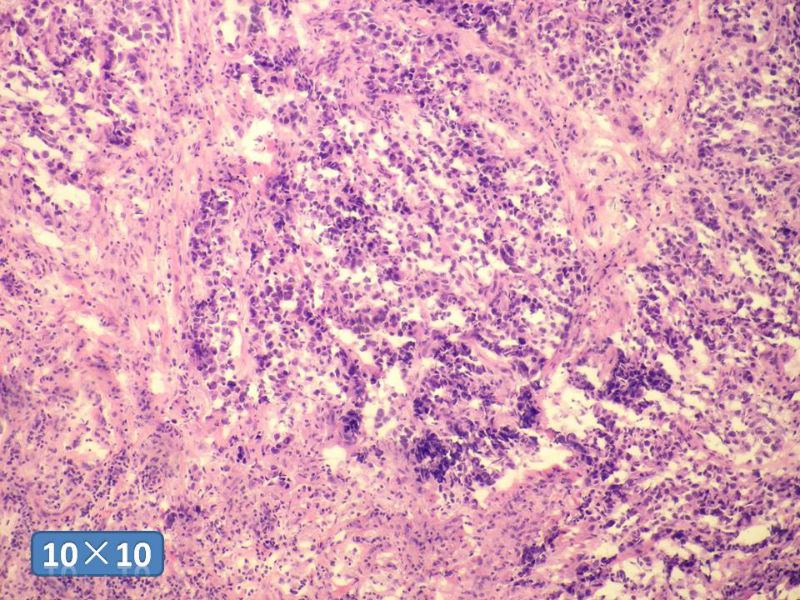

女性,50岁,乳腺肿物,冰冻切片(图1-25)

HE